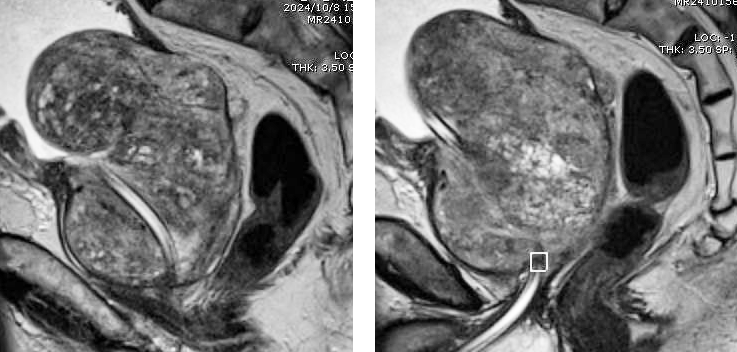

此次,患者因不愿長期留置尿管,要求行手術(shù)治療。前列腺M(fèi)RI檢查示前列腺巨大,大小為351克,且合并膀胱多發(fā)結(jié)石。一般前列腺肥大手術(shù)患者大小多在20-100克,超過200克的病例較為罕見,此例患者臨床極為罕見,為我院開展前列腺手術(shù)最大體積前列腺。一般超大體積前列腺多采取開刀手術(shù),可縮短手術(shù)時間,但開刀手術(shù)創(chuàng)傷大,術(shù)中術(shù)后出血較多,患者術(shù)后恢復(fù)慢,痛苦大,且存在膀胱漏尿,切口裂開等并發(fā)癥。